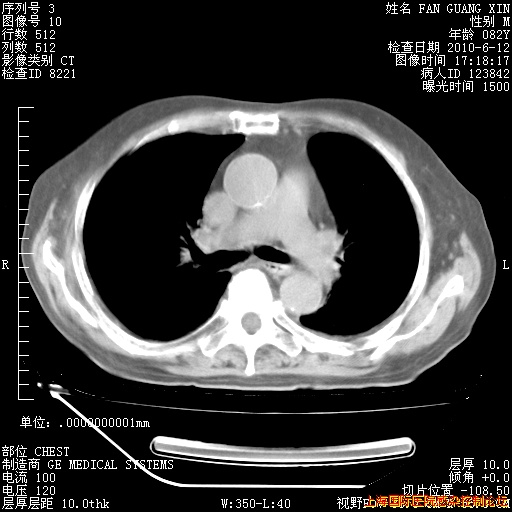

今天复查CT

今天CT

整整相隔30天的肺部CT好像有所好转啊。甲强龙减量第3天,需要观察体温。

海管,自昨日你和我通完话后,不知您岳父消化道症状有无缓解?体温怎样?阅读7.12日胸部ct,个人认为目前激素治疗是有效的,甲强龙减量是适宜的。因在抗痨治疗,需密切观察肝功、肾功能和血常规。不过,老年、长期住院和大量使用激素,很担心菌群失调发生